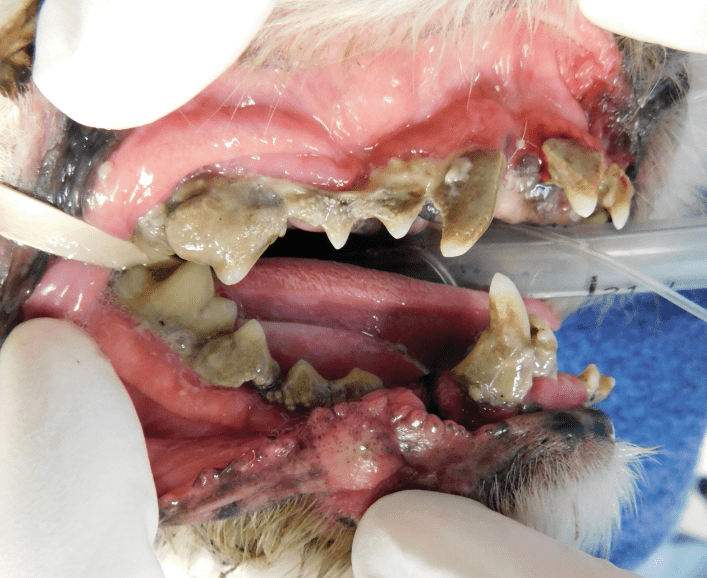

Surgical Extraction of Diseased Teeth

Periodontal disease is extremely common in dogs and cats. Over 80% of dogs and cats over two years of age have some degree of periodontal disease. Periodontal disease is best prevented by yearly professional dental cleanings starting at two years of age and at home brushing at least three times weekly. Brushing should begin at a very early age to allow your new pet to get used to regular brushing. In severe cases of infection or periodontal disease, the teeth may need to be surgically extracted. Extractions should always involve x-rays of the tooth first, as many teeth have multiple roots or may be diseased below where the eye can see. Extracting larger teeth in animals requires oral surgery, equivalent to removing wisdom teeth in people. It is vital that all of the tooth and roots be removed for the periodontal infection to resolve. In cases of important teeth with mild to moderate periodontal disease, multiple periodontal treatments can be offered to help save these teeth.